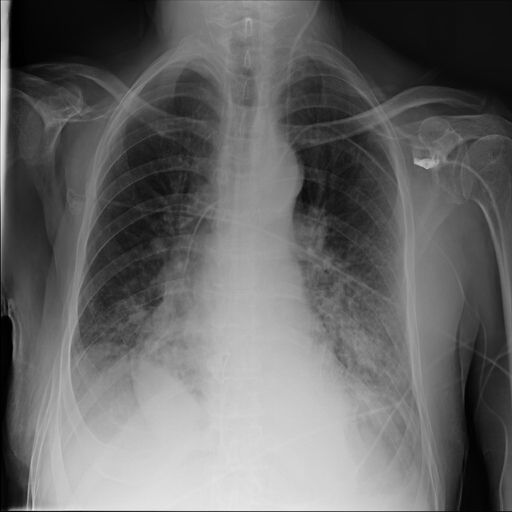

Refer to caption

(a) Original,

case 5 (simulated situs inversus).

(b) ϵ=102HWitalic-ϵsuperscript102𝐻𝑊\epsilon=10^{2}\cdot H\cdot W,

case 5.

Figure 6: Flip obfuscation with DP-GLOW.

7.2 Qualitative assessment of LDP-processed CXR images

Here, we assume two possible privacy leakage scenarios. To CXR images, we intentionally add features that can lead to the re-identification of the subject appearing in a CXR image. The first feature is an artificial block marker. The second feature is a rare anatomical abnormality known as situs inversus simulated by flipping a CXR image along the vertical axis. Figs. 3(a) and 3(c) show CXR images with the artificial block marker. Fig. 5(a) shows a flipped CXR image to represent a case of situs inversus. We applied DP-GLOW to these CXR images. In Figs. 3(b) and 3(d), the image domain LDP fails to obfuscate the artificial block marker with a moderate privacy budget. In contrast, in Figs. 4(b) and 4(d), DP-GLOW successfully obfuscated the artificial block marker with the moderate privacy budget. On the other hand, the anatomical shape of the chest and the abnormal opacity (hilar regions in the case 1) are preserved. In Fig. 5(b), we observed that the right edge of the heart does not become obfuscated with the image domain LDP. In contrast, in Fig. 6(b), we observed that the right edge of the heart becomes obfuscated and the heart appears at the center of the thoracic cage with DP-GLOW. However, DP-GLOW with this privacy budget is insufficient to almost completely erase the feature of situs inversus.